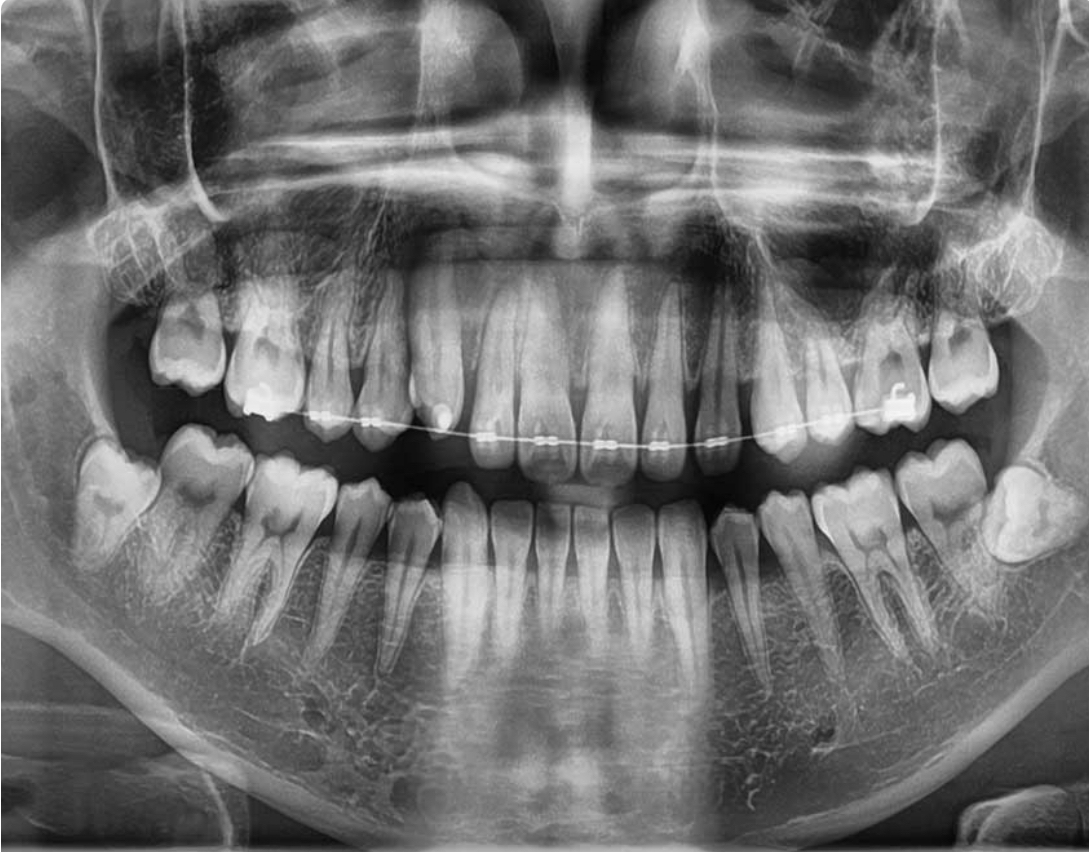

· Posedujemo rentgen kabinet za snimanje zuba (3D digitalni ortopan, Telerendgen, intraoralni rentgen sa senzorom) najnovije generacije, sa redukovanom (smanjenom) dozom zračenja!

Razlika između običnog i 3D Ortopan snimka?

3D je savremenija i bolja verzija koja stomatologu omogućava da vidi sve dimenzije mnogo bolje i postao je zlatni standard pre ugradnje implantata jer omogućava sa se vide širina kosti, visina i gustina kao i odnos prema okolnim anatomskim strukuturama kao što je npr mandibularni kanal, pod sinusa, itd, a to su sve podaci koji su neophodni za uspešnu ugradnju implantata.